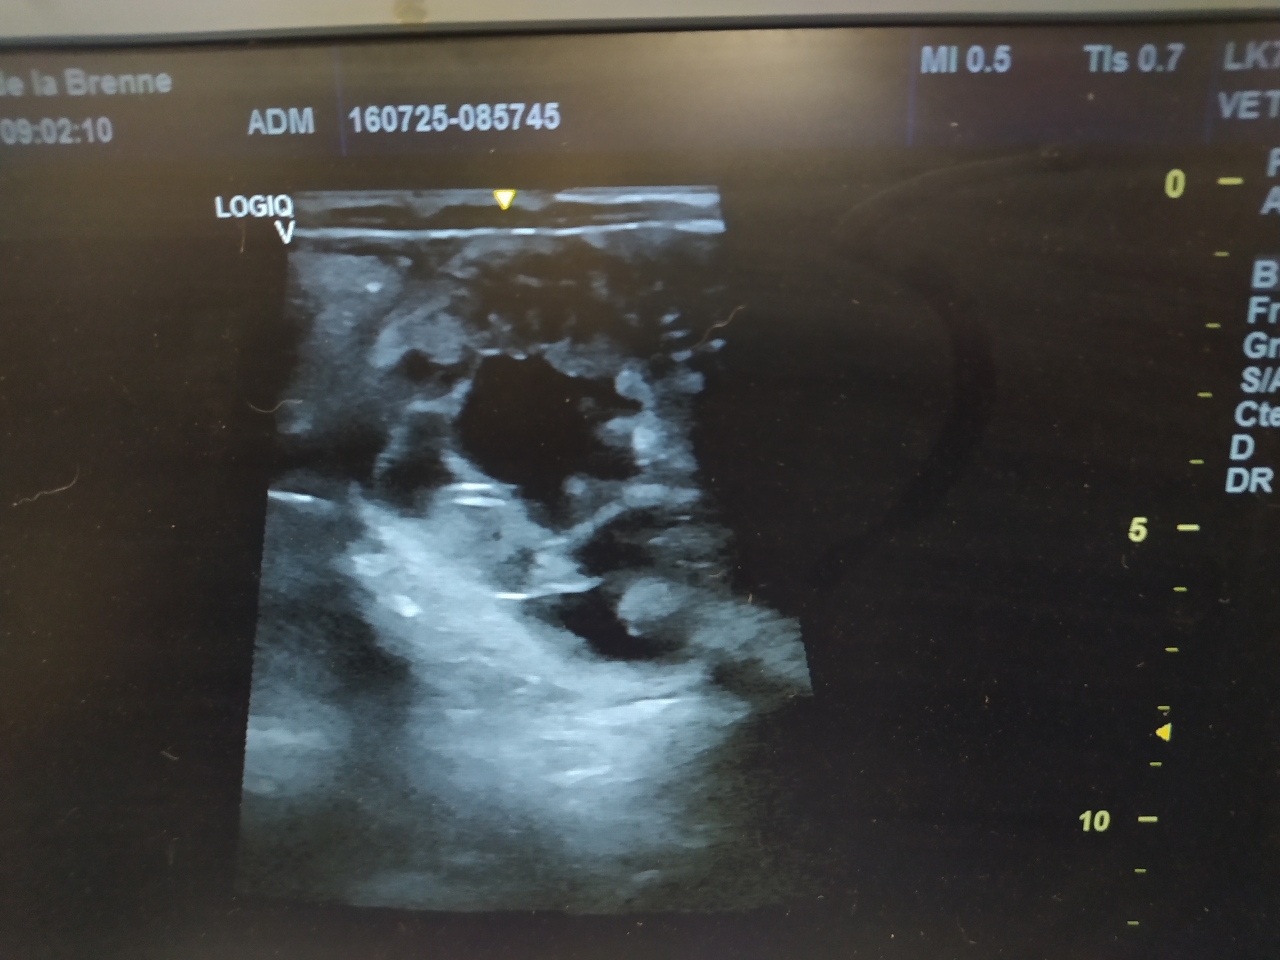

Par irisetquiara39 : le 16/07/25 à 14:30:20

| Dire merci | Ce matin, rdv pour l écho de gestation ![]() Et |